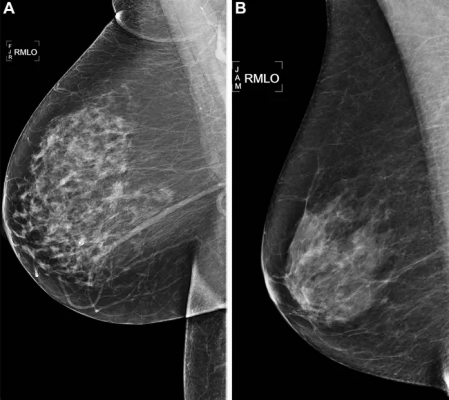

Right medial lateral oblique (RMLO) screening mammograms show negative results from 2016 in (A) a 73-year-old woman with Mirai artificial intelligence (AI) risk score with more than 90th percentile risk who developed right breast cancer in 2021 at 5 years of follow-up and (B) a 73-year-old woman with Mirai AI risk score with less than 10th percentile risk who did not develop cancer at 5 years after 5 years of follow-up. Image courtesy of Radiological Society of North America